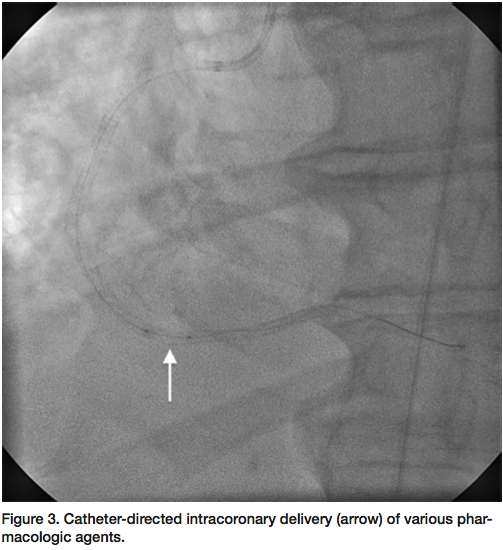

segment revealed an under-expanded stent with a reference vessel size of 4 mm. An NC Sprinter 4.0 mm balloon (Medtronic) was used to further dilate the stented segment, but with no improvement in flow. A ClearWay 1.0 x 10 mm perfusion balloon (Atrium) was then used to deliver intracoronary nitroglycerin, adenosine, and eptifibatide (Figure 3), with still no distal flow. Finally, the ClearWay balloon was used to deliver intracoronary tPA (2 mg bolus) with significant improvement in flow after 5 minutes of dwell time. Final angiogram revealed brisk TIMI-3 flow through the stented segment with excellent angiographic result (Figure 4).